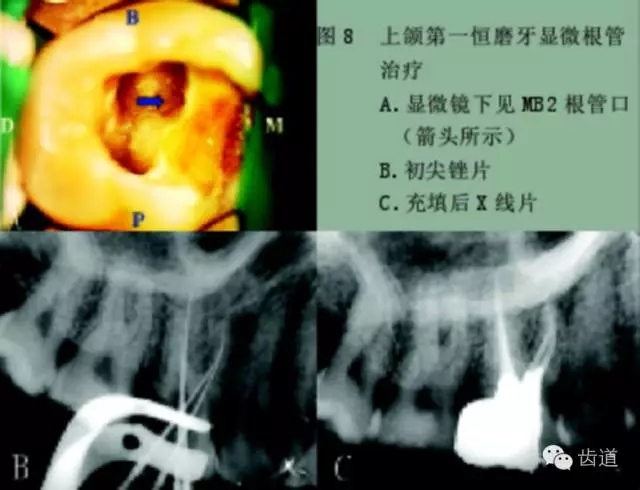

一、尋找遺漏根管

根管系統的解剖形態是極其復雜的。牙髓病學教材中常常提到磨牙有三個根管,前磨牙兩個根管,前牙一個根管。實際上,根管系統并不是如此可預知的,而是常常存在許多解剖變異。根管系統的解剖形態學研究發現:

幾乎50%磨牙中(上頜和下頜)有第四根管存在,30%以上的前磨牙有第三根管,接近25%的前牙有雙根管。

在傳統的根管治療中,開髓后往往只是依靠術者的視覺和經驗去尋找根管,所以常常存在遺漏根管的可能,從而導致根管治療的失敗。研究發現,X線片上顯示根管充填滿意的患牙仍有癥狀的主要原因是有遺漏的根管未治療。

所以對于經過完善根管治療后的牙,如果出現持續疼痛,首先應該考慮可能有遺漏根管的可能。

手術顯微鏡是用于尋找隱藏或遺漏的根管最重要的工具。因為手術顯微鏡能夠幫助醫生觀察到肉眼或普通放大鏡無法分辨的根管口和微小病損。在手術顯微鏡下,利用高倍數(16~24倍)的放大作用以及理想的照明條件,仔細檢查患牙的髓室底,許多細微的解剖結構能容易被發現。

為了光線能充分進入髓腔,髓室頂應完全揭去,開髓口的形態應根據具體牙位進行適當修改,使得所有根管口都能夠充分暴露。同時,對髓底進行美藍染色也有助于根管口和微小病損的識別。

對于有些牙根管在根管口下3~5毫米處分叉以及近頰和遠頰根管口非常接近的上頜第二磨牙,手術顯微鏡更是相當有價值的工具。因為根管的分叉點和獨立的根管口能清楚地在顯微鏡下被觀察到。